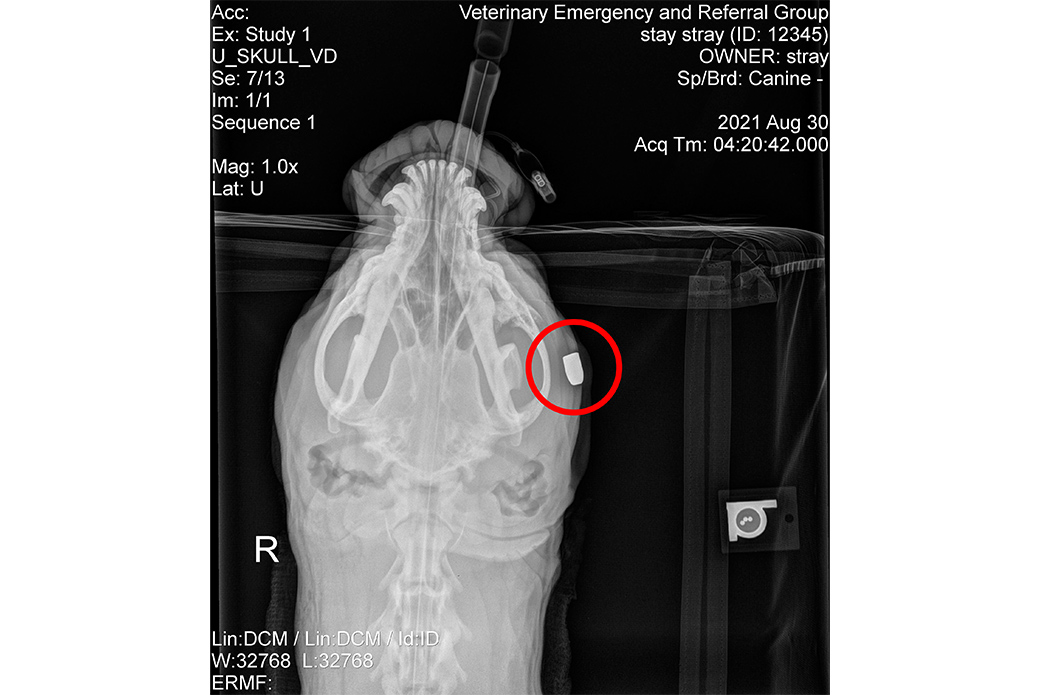

Having been shot in the face and neck, Autumn was rushed to the Veterinary Emergency and Referral Group (VERG) and quickly triaged. The veterinary team at VERG then performed a procedure to remove the bullet.

“Medically, this dog is a miracle,” says Dr. Aubrey Crowley, Medical Supervisor at the ASPCA Animal Recovery Center (ARC). “She was shot in the face and neck, and the bullet managed to avoid all major structures and lodged in her left cheek.”